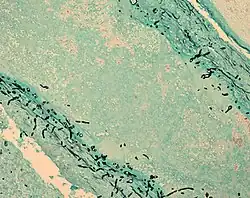

Fungal cells (black lines) in infected brain tissue (cyan) | |